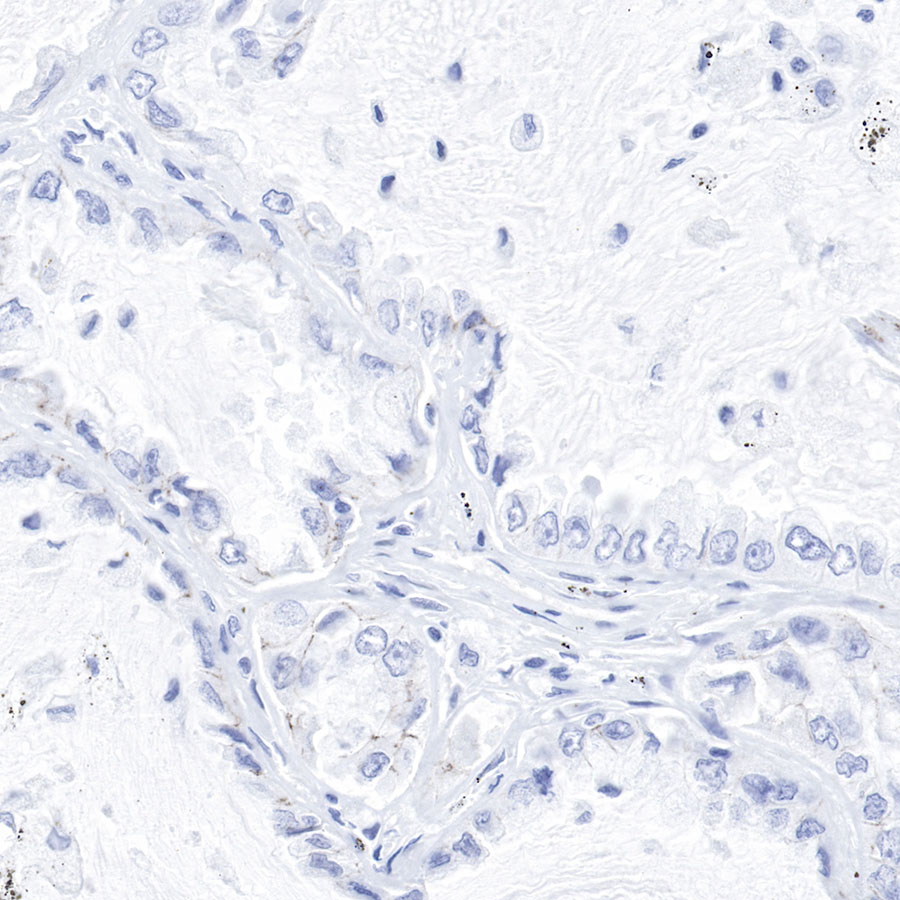

Negative control: ICC shows negative staining in MCF7 cells.

Anti-Claudin-1 antibody was used at 1/250 dilution and incubated overnight at 4°C. Goat polyclonal Antibody to Rabbit IgG - H&L (Alexa Fluor® 488) was used as secondary antibody at 1/1000 dilution.

The cells were fixed with 100% methanol and permeabilized with 0.1% PBS-Triton X-100.

Nuclei were counterstained with DAPI.